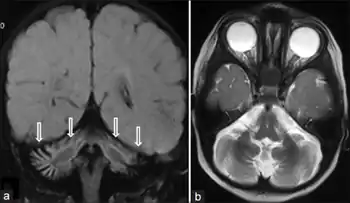

SIL1-negative Marinesco-Sjögren syndrome a,b) MRI coronal and axial image shows cerebellar vermian and hemispheric atrophy

Diagnosis of MSS is based on clinical symptoms, magnetic resonance imaging (MRI) of the brain (cerebellar atrophy particularly involving the cerebellar vermis), and muscle biopsy.